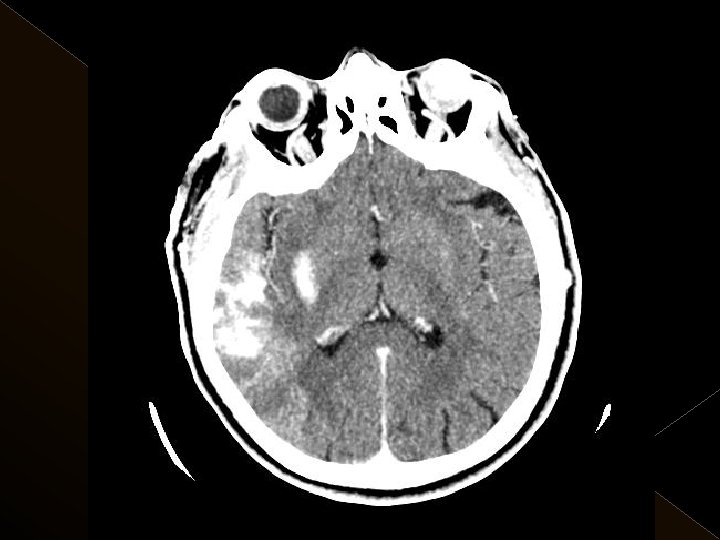

Görüntüleme İşlem öncesi § Bazal kontrastsız BT § BT anjiografi (varsa perfüzyon BT ) § MR (DW, ADC) İşlem sonrası § MR ( DW, ADC, SWI) § 24. saatte kontrol BT veya MR

KOMPLİKASYONLAR Ponksiyon bölgesi komplikasyonları � Trombektomi stentine ait komplikasyon (*1) � Diseksiyon(*2) � Karotikokavernöz fistül (‘ 1) � Hemorajik komplikasyonlar(‘ 5) Semptomatik-nonsemptomatik � İskemik komplikasyonlar (3) � Reoklüzyon (2 i. a) � Kontrast madde nefropatisi �